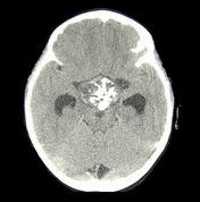

Для оценки тяжести поражения костной системы проводится рентгенография костей стоп, кистей, голени, черепа, денситометрия. Типично выявление признаков диффузной деминерализации костной ткани или фиброзно-кистозного остита. При обзорной урографии, УЗИ почек и мочевого пузыря обнаруживаются одиночные или множественные камни. Состояние органов пищеварения оценивается с помощью УЗИ брюшной полости (желчного пузыря, поджелудочной железы), ЭГДС. При сердечно-сосудистой симптоматике показано выполнение ЭКГ, ЭхоКГ, суточного мониторирования ЭКГ и АД.